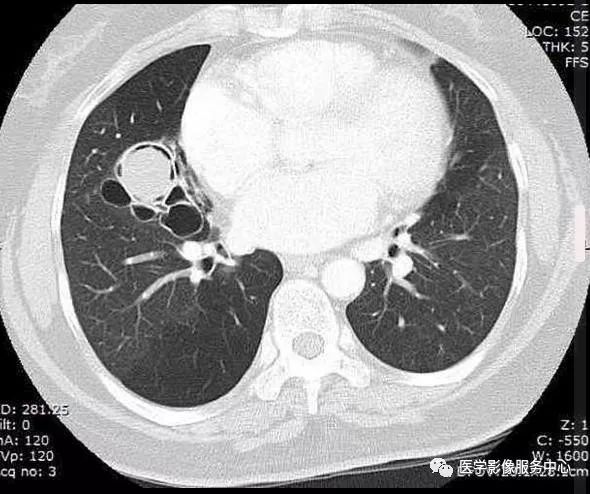

CT:右肺中叶见一个球形软组织密度影,周围见空气新月征

(1)致密阴影在空洞内随体位的改变而移动。在直立的胸部x线片,空气新月征位于致密阴影上;然而,在患者仰卧的CT图像上,空气新月征位于致密阴影前。

CT:初为肺部局限性炎症,表现为斑片状模糊阴影,继发周围炎症吸收,表现为团块状或结节状阴影,周围环以浅淡的磨玻璃样的晕,当肺组织液化,坏死物咳出后,则表现为:新月状的空气所包绕的一致密阴影,该致密阴影边缘光整,密度较均匀,增强无强化,且致密阴影在空洞内随体位的改变而移动。